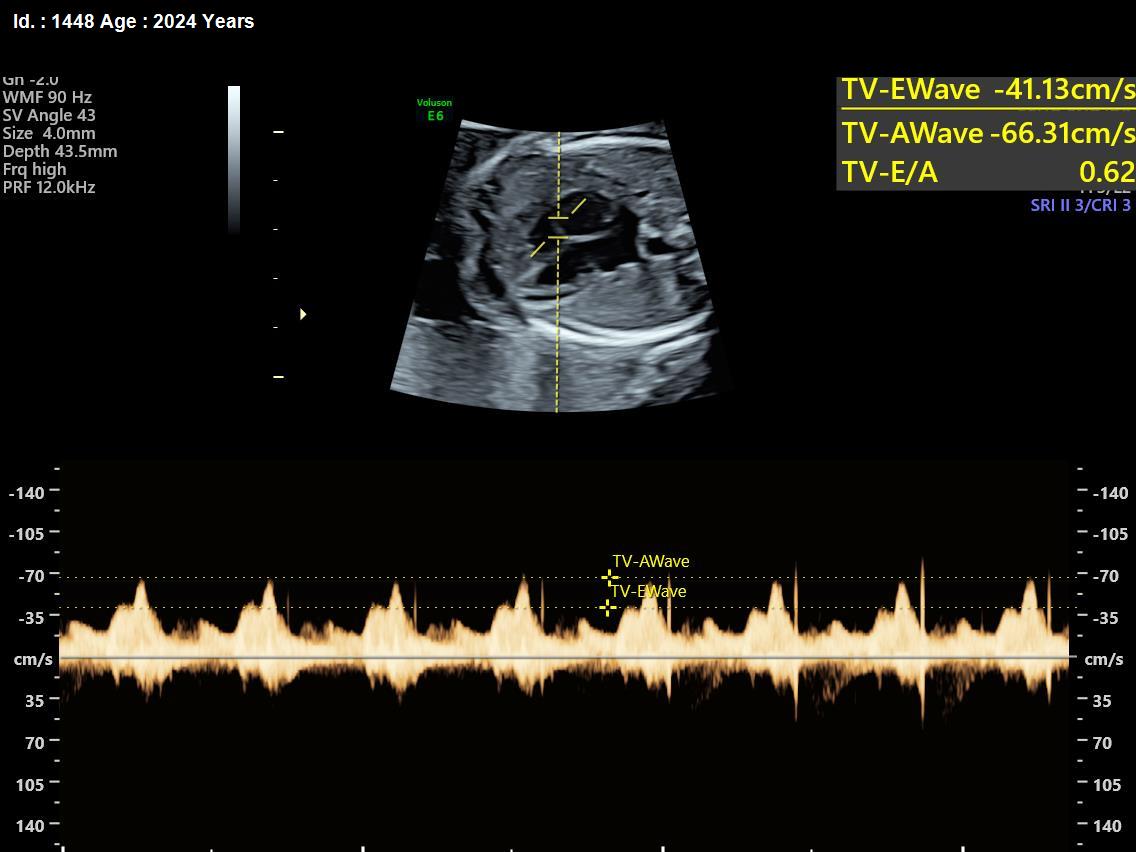

It is a test similar to ultrasound. It allows the doctor to see structure and function of the baby’s heart in detail. It also enables the doctor to see blood flow through fetal heart and cardiac rhythm. The scan is done by a radiologist or a fetal medicine specialist.

A fetal echocardiogram focuses specifically on the fetal heart, providing a detailed examination of its structure and function. In contrast, a standard ultrasound assesses overall fetal development and growth.